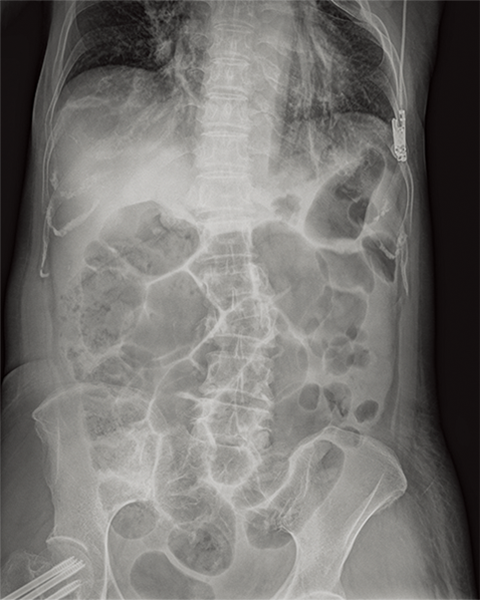

Multiple body parts supported

Abdomen

Cervical Spine

Thoracic Spine

Lumber Spine